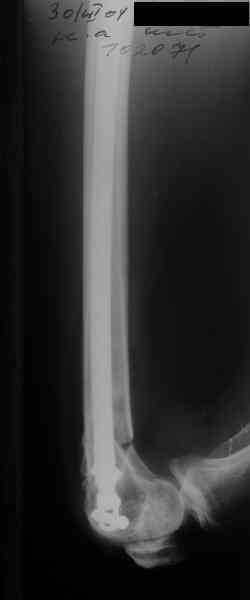

I> Насчет снимка Вами представленного - смотрится оч красиво, еще бы на

I> функцию узнать...

В приложении функциональные снимки в 3 мес. и в 1 год.